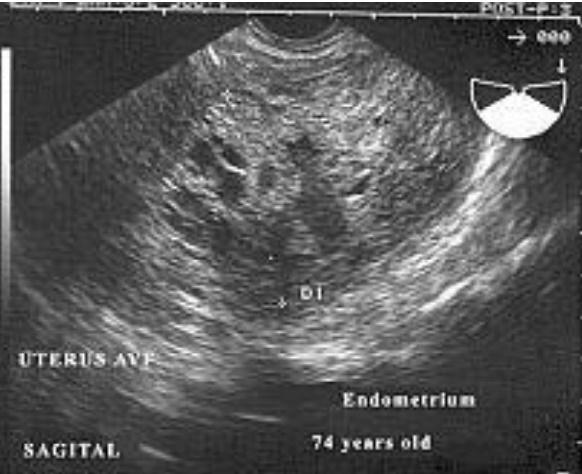

Patologías de Endometrio

Carcinoma Endometrial

Adenocarcinoma – frecuentes en la etapa

peri y post-menopáusica.

Signo más temprano engrosamiento de endometrio

El diagnóstico es más certero si hay engrosamiento, agrandamiento, alteración del contorno y cambios en la ecogenicidad del endometrio.

Cáncer Endometrial

Aquellas pacientes con

hiperplasia endometrial están más propensas a desarrollar éste tipo de cáncer.

Cáncer Endometrial (imagen)